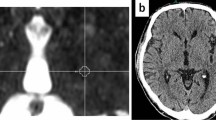

Targets other than the thalamus have been treated with HIFU for relief of other signs and symptoms of PD. Unilateral lesions were created with HIFU in 13 patients with PD targeting the fiber tracts exiting the pallidum on route to thalamus (pallidothalamic tract), including the fasiculus lenticularis and ansa lenticularis [2]. Although the initial patients treated had rapid return of PD symptoms associated with insufficient increases in target temperature, increasing the ultrasound energy resulted in a 60% reduction in Unified Parkinson’s disease rating scale scores in 9 subsequent patients. This group of patients was heterogeneous with regard to aspects of PD (tremor, bradykinesia, dyskinesias) that dominated their clinical picture. Improvement persisted during the 3-month follow-up. As in the vast majority of MRgHIFU studies, postprocedure MRI showed a lesion at the site that received adequate thermal energy (Fig. 2, from Magara et al. [2]). These MRI changes diminish after time, but reversal of lesions visible with MRI does not correlate well with the duration of clinical effect.

Magnetic resonance imaging (MRI) of focused ultrasound-induced lesions. A comparison of the different MRI scans available to visualize thermally induced lesions in the pallidothalamic tract in 2 different patients undergoing MRI-guided focused ultrasound-mediated pallidothalamic tractotomy, and at 2 different times post-treatment. At 3 months post-treatment, a lesion can still be seen only in patient 5 (arrow). T2-w = T2-weighted; T1-w = T1-weighted; SWAN = T2 star weighted angiography; DTI = diffusion tensor imaging. (Reprinted with permission from Magara et al [2])